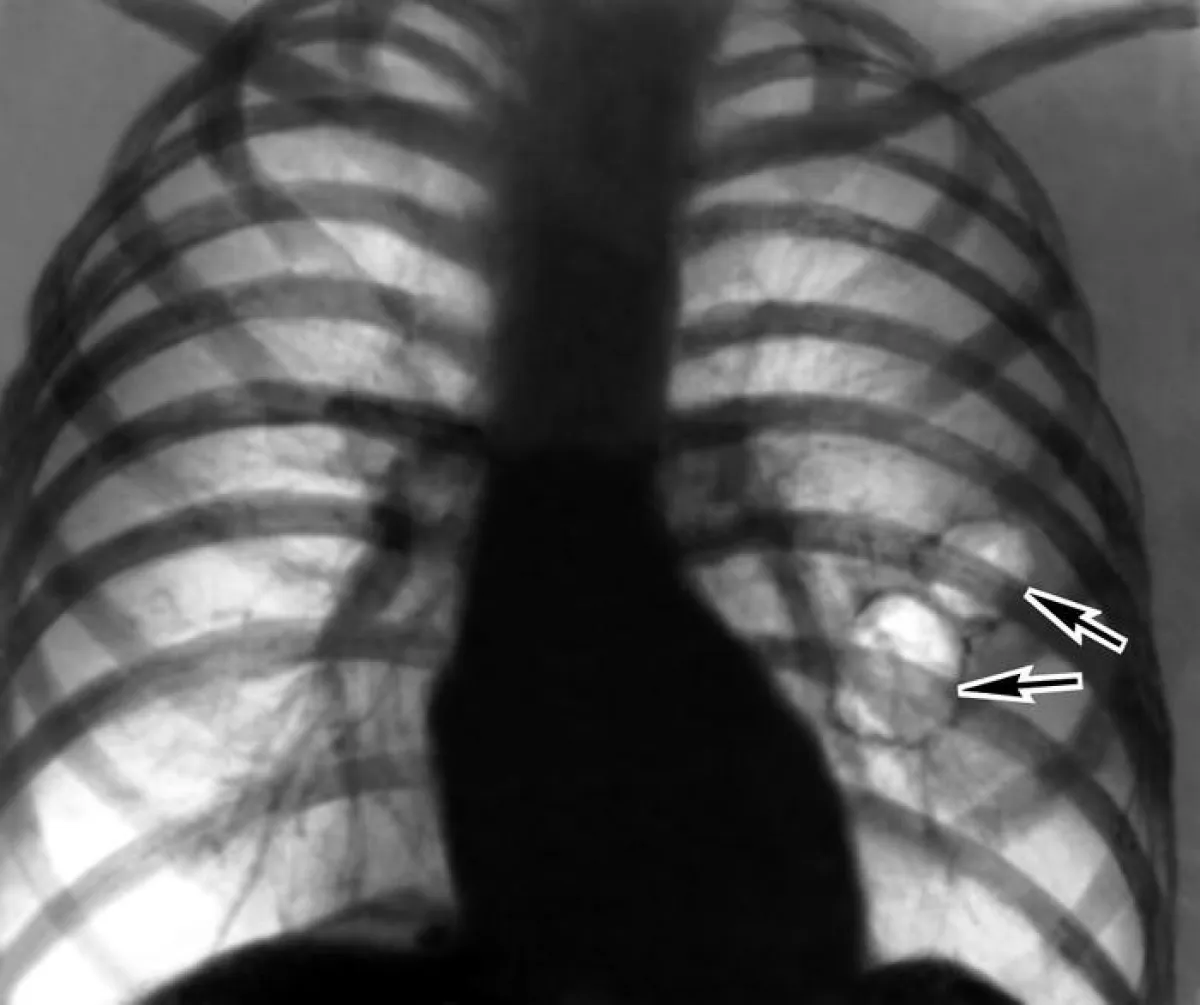

وأوضحت الدراسة، التي أعدها باحثون في جامعة كاليفورنيا الأمريكية أن الأبخرة المتصاعدة من السجائر الإلكترونية ترتبط بصورةٍ كبيرةٍ بخطر الإصابة بأمراض الرئة مثل الربو والتهاب الشعب الهوائية وانتفاخ الرئة.

وأوضحت الدراسة أن المشكلة الرئيسية في التدخين الإلكتروني، هو دخان الزيوت المتصاعد من تلك السجائر، والذي يترسب داخل الرئة، وسبب مخاطر أكبر بكثير من تدخين التبغ التقليدي.